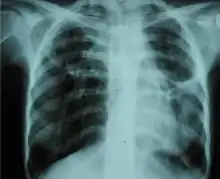

A fibrothorax can typically be diagnosed by taking an appropriate medical history in combination with the use of appropriate imaging techniques such as a plain chest X-ray or CT scan.[3] These imaging techniques can detect fibrothorax and pleural thickening that surround the lungs.[7] The presence of a thickened peel with or without calcification are common features of fibrothorax when imaged.[3] CT scans can more readily differentiate whether pleural thickening is due to extra fat deposition or true pleural thickening than X-rays.[3]

If a fibrothorax is severe, the thickening may restrict the lung on the affected side causing a loss of lung volume.[7] Additionally, the mediastinum may be physically shifted toward the affected side.[3] A reduction in the size of one side of the chest (hemithorax) on an X-ray or CT scan of the chest suggests chronic scarring.[6] Signs of the underlying disease causing the fibrothorax are also occasionally seen on the X-ray.[6] A CT scan may show features similar to those seen on a plain X-ray.[7] Lung function testing typically demonstrates findings consistent with restrictive lung disease.[6]

Extensive left-sided fibrothorax

Chest radiograph displaying inhomogeneous opacification of the left half of the chest that is fibrothorax